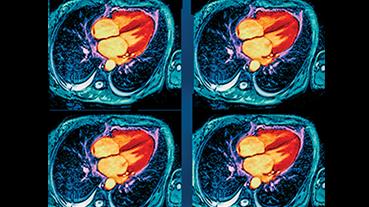

In 2025, cardiologists and cardiac surgeons at NewYork-Presbyterian led breakthroughs that impacted a range of diseases and conditions from advanced heart failure to pediatric valve disease. Physicians and researchers from Columbia and Weill Cornell Medicine pioneered the use of artificial intelligence to identify structural heart disease, launched a mobile app to expand access to heart failure education, performed one of the first split-root domino partial heart transplants, and more. Our experts remained at the forefront of innovative, multidisciplinary care, delivering comprehensive treatment for the most complex cardiac diseases.

Our world-renowned Columbia and Weill Cornell Medicine physicians and surgeons in our comprehensive cardiology, heart surgery, and vascular programs spearhead groundbreaking clinical and scientific research and provide the most innovative treatments to optimize patient outcomes for all stages of disease complexity. Our clinicians are experts in minimally invasive approaches and novel therapeutics for all types of heart disease and work across disciplines to provide compassionate care to all patients.